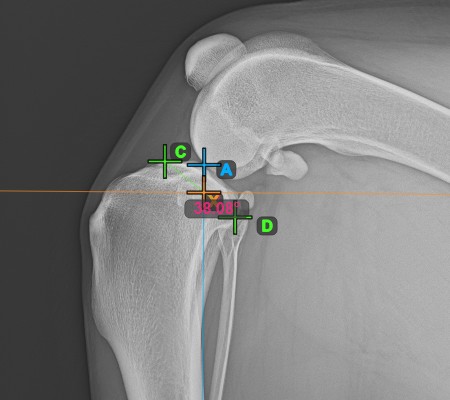

Vervollständigen Sie den TPA-Winkel, indem Sie den hintersten Punkt des Tibiakopfes (Tibiaplateau) markieren. Der TPA-Winkel wird automatisch als der Winkel zwischen der Linie, die die beiden Punkte am Tibiaplateau verbindet, und der senkrechten Linie zur Längsachse der Tibia berechnet.

Das Bild unten zeigt die übliche Platzierung des hintersten Punkts am Tibiaplateau und die automatisch berechnete TPA-Winkel-Messung.